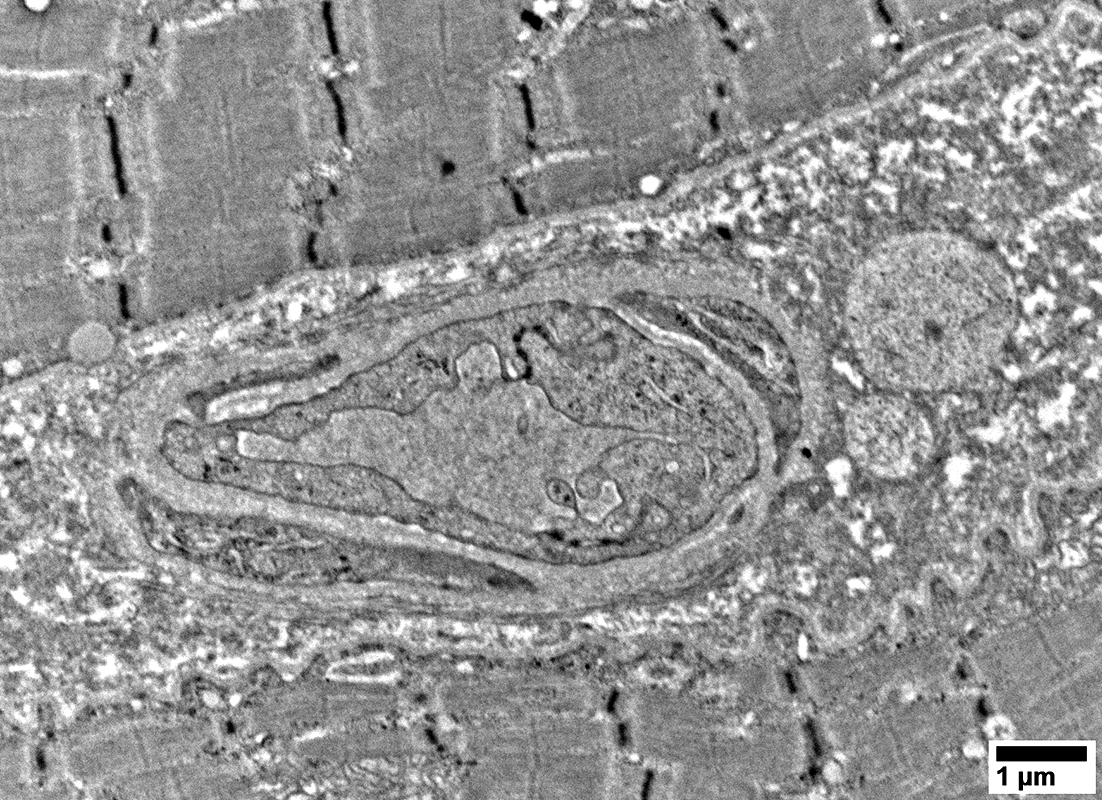

Sarcomere structure

Normal

Mitochondria

Often large

From: R Schmidt